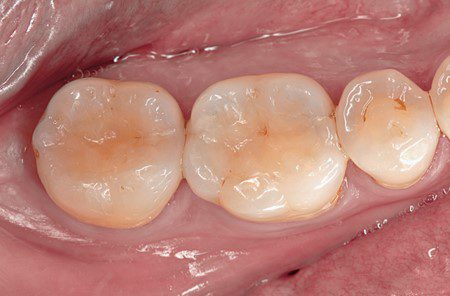

Hình 10. Hình ảnh mặt nhai sau điều trị cho thấy sự tích hợp hài hòa giữa hình dạng giải phẫu và độ sâu bên trong của màu sắc.

Hình 11. Tái khám sau 2 năm và 5 năm. Lưu ý độ mòn nhẹ ở bờ viền R47.